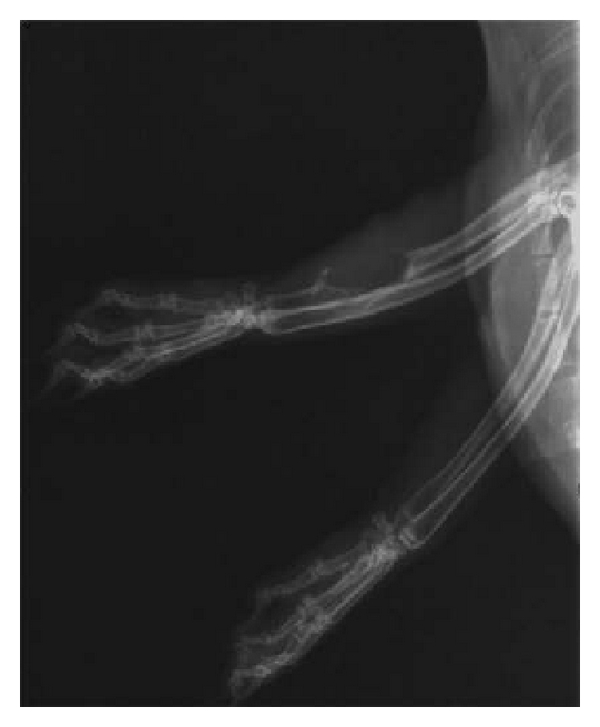

3.2. X-Ray Radiation Examination

X-ray radiation examination was conducted on right upper limb of 30 New Zealand rabbits immediately after surgery. Sufficient amount of scaffolds had been implanted into the bone defect site and the diameter of scaffold was bigger than ulna, indicating that it is a successful modeling for New Zealand rabbits bone defect. Small callus tissue and remaining scaffold can be observed in group A and group B 1 month after implantation; at the same time, periosteal proliferation was found in samples in group C. There was no statistically significant difference among three groups () according to chi-square test. At 2 months, plenty of calluses were expansively grown in group B; big callus volume was formed at the terminals of defect site in group A; no callus was formed in 8 samples of group C, and the difference among three groups was statistically significant () according to chi-square test. After 3 months, the volume of callus in group B was bigger than group A, and group C had marrow cavity sclerosis and bone atrophy which was typical bone nonunion performance. The difference among three groups was also significant (). The effective rate in group A was 14.29% (1 of 7 ulnas was healed), while the effective rate of group B was 33.33% (2 in 6). We excluded 2 dead rabbits in each group which was selected for histology HE staining test in the first 2 months. Figure 2 shows the example radiographs obtained at the 3rd month after surgery in three groups.

(a)

(b)

(c)